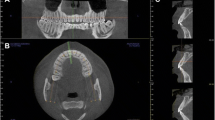

The arch form selector tool was centred throughout the middle of the arch in the coronal plane at the cement-enamel level selecting the centre of the nerve canal of single root teeth and the middle of the interradicular septum of multirooted teeth (Fig. 1). The thickness of the alveolar bone was measured after selecting the cross-sectional image made at the midpoint of the tooth, at which the centre of the root canal passes, parallel to its long axis (Fig. 2). To perform the measurements, sagittal scans from the reconstructed data were selected, resulting in images where the entire root and cementoenamel junction (CEJ) were present for single rooted teeth. Two different slices were selected for multirooted teeth, one which passed across from the apex of the mesiobuccal and the distobuccal root. The long axis determined the slice. The captured images had a resolution of 72 pixels/inch and were saved with the standard zoom of Planmeca Romexis [20] viewer and exported to Photoshop CS5 to be measured. All the images had a lateral ruler which served to the surgeons for calibrating the measurements made on the photo editor to the distance at the DICOM images.

CBCT images were analysed on two computers, both with Windows 7 and Intel core i-7 processors with a monitor resolution of 1366 × 768. Data were reconstructed with an image size of 401 × 401 × 401, voxel size 200 μm, 90 Kv, 14 mA, 12,249 s and DAP 12,3 (mGyxcm2).

The present transversal descriptive study included CBCT images obtained by an x-ray device (Planmeca ProMax 3D; Planmeca Oy; Helsinki, Finland) using a spiral technique with 0.2 mm thickness (200 μm voxel size, 200 mm field of view (FOV), 90 kV, 10 mAs, 1 mm pass) from patients referred to the Periodontology Department of Dental School of Seville for implant therapy from January to December 2014. The ethical committee for the University of Seville approved this non-interventional study for the acquisition of the images, number 0159-N-14 (PEIBA) of the Junta de Andalucía, Spain. The inclusion criteria are described in Table 1.